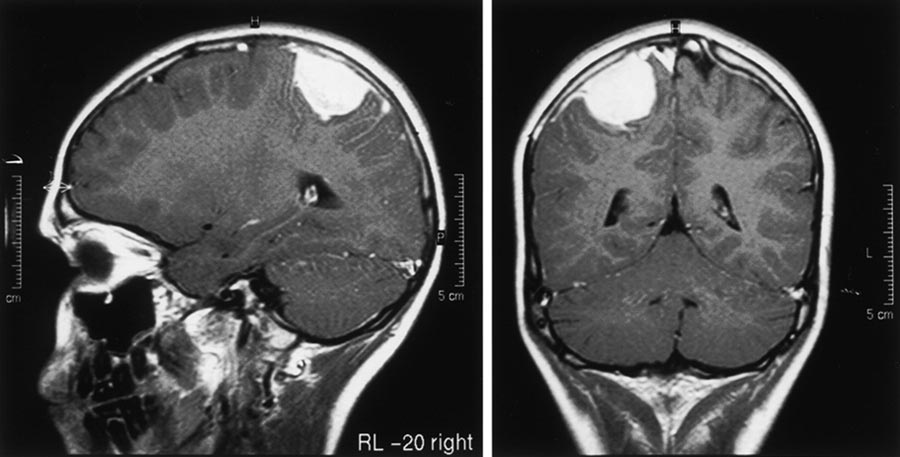

Meningioma